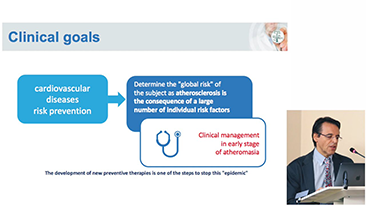

??g?rĂŒler

GĂŒnĂŒmĂŒzde t?bbi ortam daha karma??k hale geldi, zorlu vakalar?n say?s? ve i? yĂŒkleri artt?.